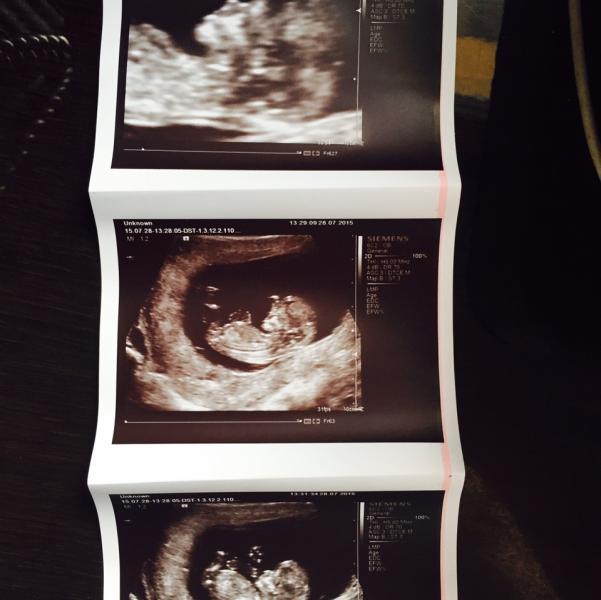

Сегодня мы сделали долгожданный скрининг, услышала как бьётся сердечко моего чуда, разглядела со всех сторон, это такое счастье не передаваемое🙏🏻🙏🏻🙏🏻😍😍😍❤️❤️❤️ Всем желаю всего самого доброго🙏🏻🙏🏻🙏🏻

Да, у меня аж слёзки пошли🙈😍 Да в род доме у Бабчинской, очень понравилась🙏🏻🙏🏻🙏🏻 (500 руб. сразу в карман) Мне так проще и спокойней как-то🙈

Здорово!!!! Тоже скорее хочу на скрининг 😍 вы в род доме делали? Пол вам сказали?